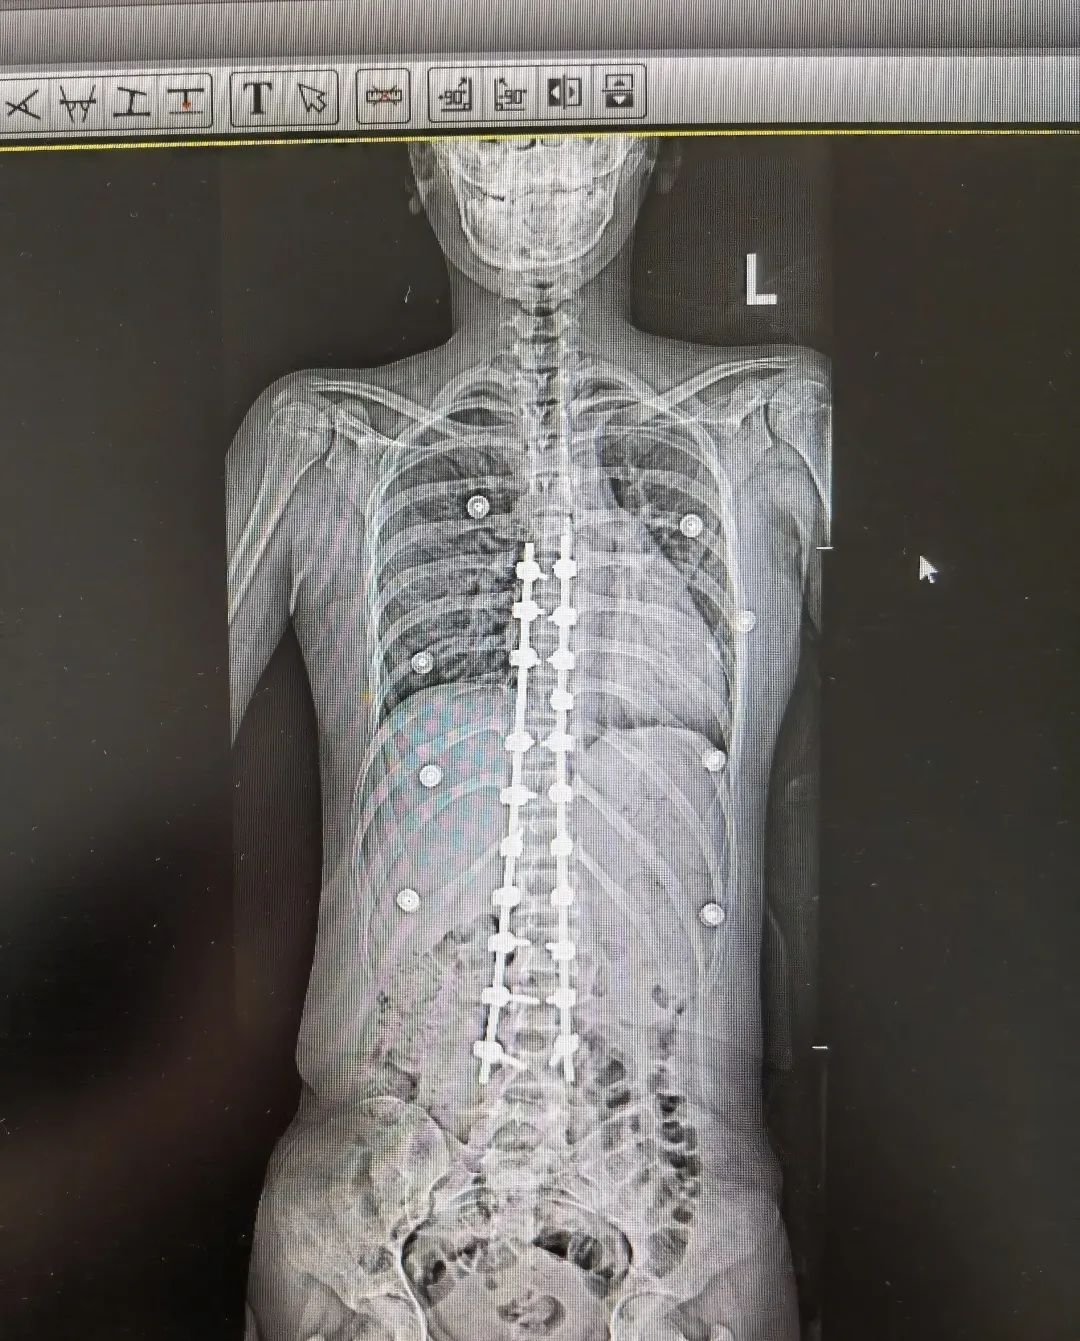

先天性脊柱侧弯半椎体畸形术前术后图

陈文昊副主任介绍,每个人的脊椎由两个成骨中心,两边合在一起,逐渐成为一个椎体。如果只有一侧成骨,则形成半个椎体。半椎体引起的脊柱侧弯和孩子平时的坐姿不良没有关系,它是由于脊柱在胚胎时期出现脊椎的分节不完全、一侧有骨桥或者一侧椎体发育不完全或者混合有上述两种因素,造成脊柱两侧生长不对称,从而引起脊柱侧弯。

“家长需要注意的是,如果孩子还没到青春期,就发现有脊柱侧弯的倾向,就要考虑是否可能是先天因素引起,建议带孩子到医院进行排查,而不是简单归为坐姿问题,不然可能会延误治疗。”陈文昊说。